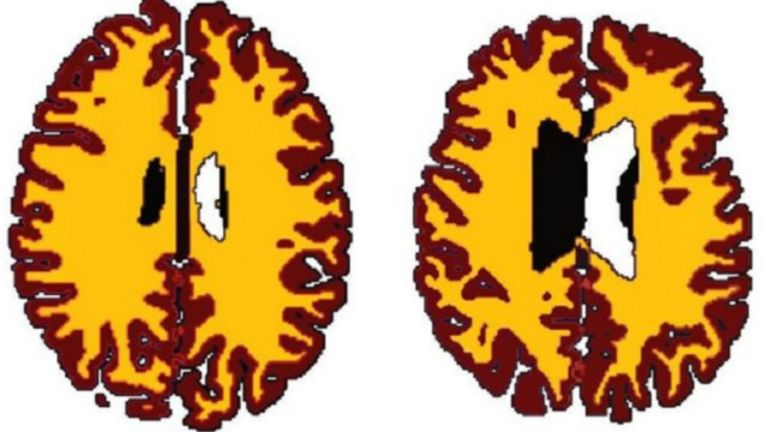

تقل المادة البيضاء مع تقدم السن

وبشكل طبيعي مع تقدم السن تفقد الأدمغة المادة البيضاء - جزء الدماغ المسؤول عن نقل الايعازات العصبية.

ووجدت النتائج التي نشرت في دورية علم أعصاب الشيخوخة، فروقا هامة في حجم المادة البيضاء في أدمغة الأشخاص الذين يعانون من زيادة الوزن مقارنة بالأشخاص الأقل وزنا.

وكانت المادة البيضاء في أدمغة زائدي الوزن أقل بكثير منها عند نظرائهم الأقل وزنا.